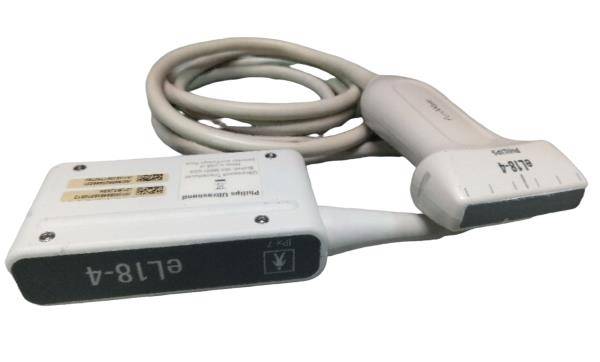

Probe Function: 3.5MHZ convex, abdominal organs

Probe 2: 7.5MHZ Transvaginal probe:gynecologic examination

The Diagnostic Ultrasound Scanner provides a comprehensive solution for medical practitioners. It includes both convex and transvaginal probes, allowing for versatile imaging options. With the ability to create detailed images of various organs, this machine significantly improves diagnostic accuracy. Moreover, doctors can perform thorough examinations quickly and easily, so they can identify medical conditions early. As a result, patients receive timely care that can lead to better health outcomes.